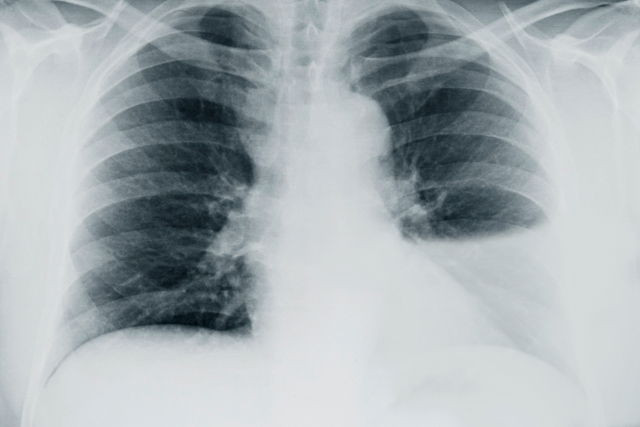

Derrame Pleural: Como Identificar Sintomas, Diagnóstico e Especialistas Indicados

Descubra especialistas em derrame pleural, sintomas, diagnóstico e tratamento. Saiba qual médico consultar e opções terapêuticas disponíveis.

Derrame Pleural: Causas, Sintomas e Tratamento Eficaz

Descubra o que é derrame pleural, seus sintomas, causas e tratamento eficaz. Entenda como identificar e lidar com essa condição.